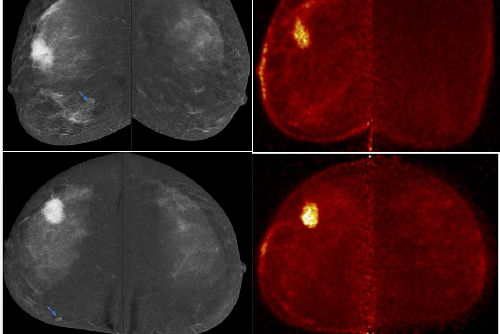

Namely, individuals receiving theranostic treatments not only receive therapeutic drugs but also radiotracer injections and undergo multiple PET scans and dosimetry imaging, which involves multi-timepoint SPECT scans. Add typical labs for oncology, and all of this adds up, Bradshaw said.